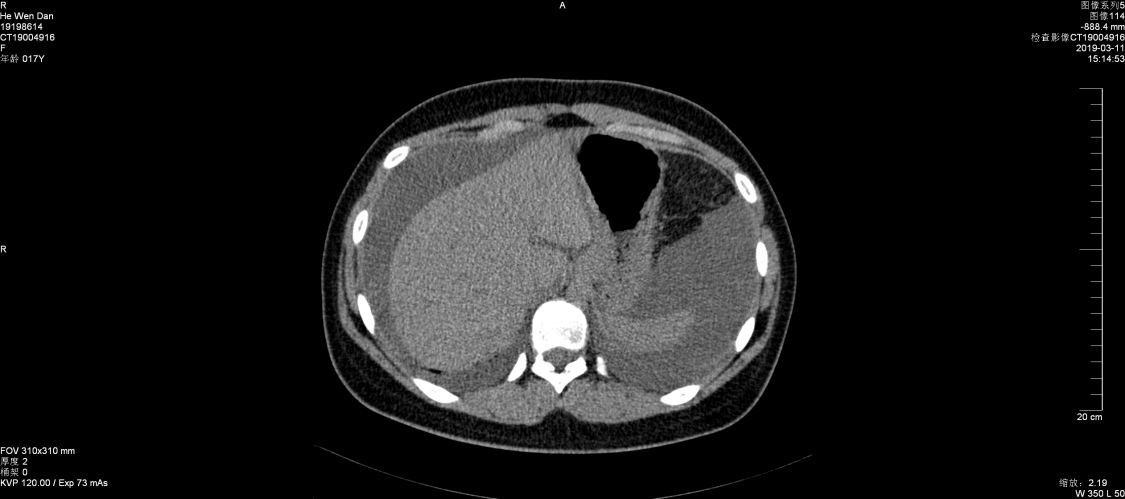

2019年3月11日,消化内科收治一名女性患者,16岁,以“腹胀1周、腹泻、腹痛1天”之主诉入院,查体:生命体征平稳,皮肤未见皮疹,心肺未见异常,腹部有柔韧感,无明显压痛,移动性浊音阳性。B超提示盆腔、腹腔积液,门诊按“急性胃肠炎”收治。入院后检查结果,血常规:白细胞22.52×109/L,嗜酸细胞比率21.2%,最高达48.6%。嗜酸细胞计数:10.81×109/L,B超提示腹膜增厚,伴大量腹水。胃镜检查:胃窦部粘膜充血、水肿,幽门狭窄,疑幽门梗阻,胃镜活检可见大量嗜酸细胞浸润。